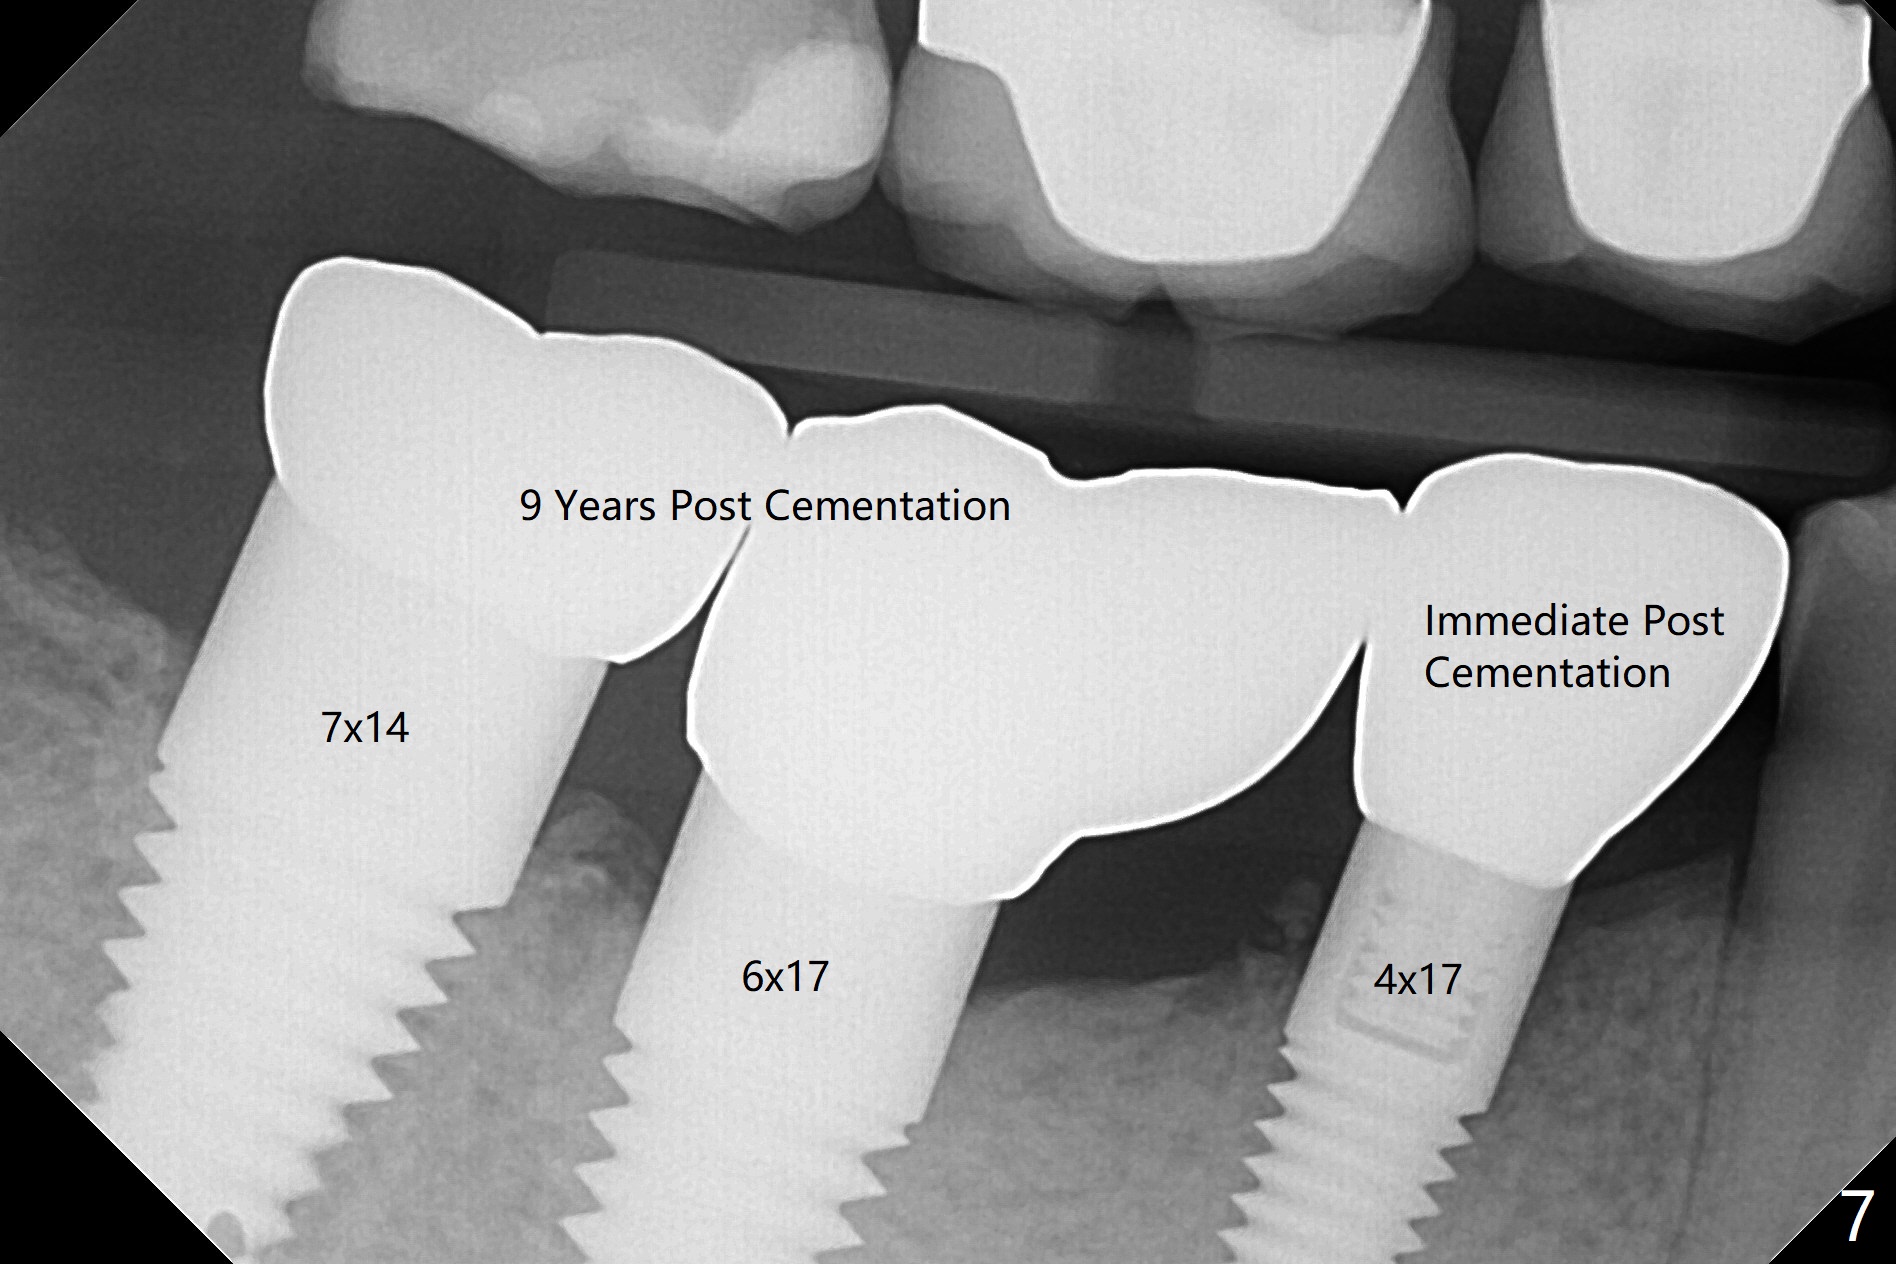

徒手即刻种植缺点是钻洞深度控制不易,尤其是术前设计是骨水平植体,而术中决定使用软组织水平植体。当3毫米reamer达到14毫米深度(骨水平)时,略感到根尖骨质长度。可欣的是4乘17毫米软组织水平植体取得初步稳定性(图二),即刻放置基台(3.5乘5毫米)后,骨粉放入颊侧间隙,有意地把骨粉推向远中(图二:*),好像植体接近颏神经(图二:红色),不过术后没有神经麻木现象,术后分析术前CT表明植体离神经相当远(图三)。术后四个月病人回来做修复,这时我们不关心深部神经了,重点是牙槽嵴周围骨质与植体愈合如何。可以使用sensor 1 (一号传感器,图四:1)和根尖片固定器(黄色,这样减少病人疼痛,恶心,容易放置,拍摄影像好,平行)或者sensor 2(图四:2)加咬翼片固定器(红色,同样容易放置,拍摄影像好,平行,植体螺纹清晰);为了拍摄下颌牙齿多些,传感器放低些(相对于固定器,图四,五),结果得到的信息足够(图六),好像植体已经整合,接着取模。There is no residual cement immediately post cementation with a small escape hole occlusally (Fig.7).